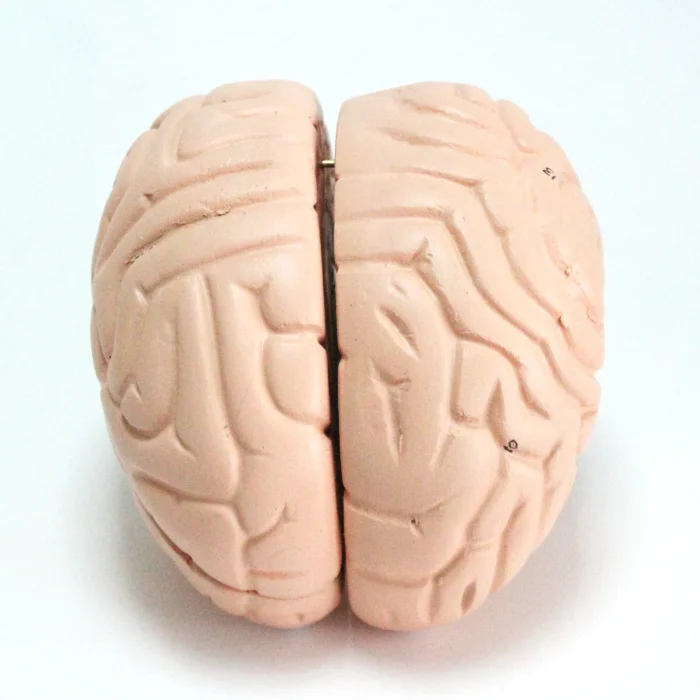

Modèle anatomique de cerveau humain

Modèle de cerveau humain

4 parties : (Fabriqué à partir de fibre de verre)

Modèle anatomique de cerveau humain

4 parties : (Fabriqué à partir de fibre de verre)

Ce cerveau est médialement divisé en deux parties, la moitié droite peut être démontée en frontal avec les lobes parentaux, le tronc cérébral avec les lobes temporaux et occipitaux en deux parties. Placé sur une base amovible avec Key Card numérotée.